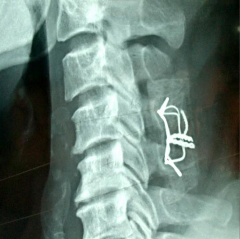

BÁN TRẬT C5-C6 (8-4-2003)

Mỏm khớp dưới cởi lên đỉnh mỏm khớp trên.

C5 di lệch ra trước. Gập góc mở ra sau. SAU MỔ: Nắn, cố định tốt

SAU MỔ 3 THÁNG (25-7-2003)

NGHIÊNG (Tái tạo đường cong sinh lý) THẲNG (Chỉ thép vẫn tốt)